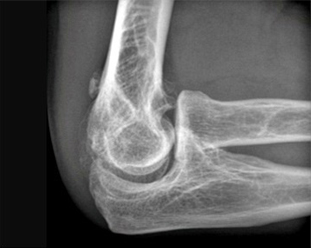

뼈 제거술 전